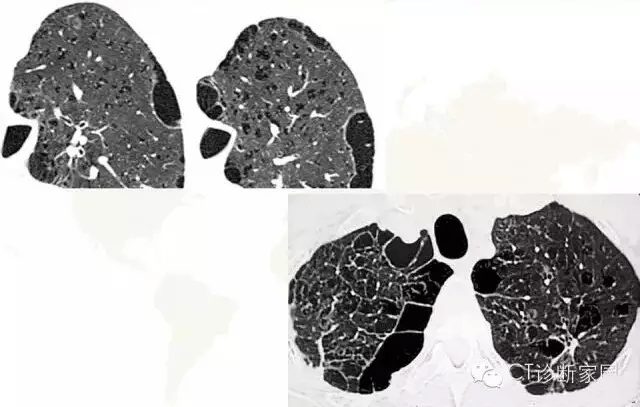

ct经典图谱肺气肿ct典型图谱一学就会

图片尺寸790x766